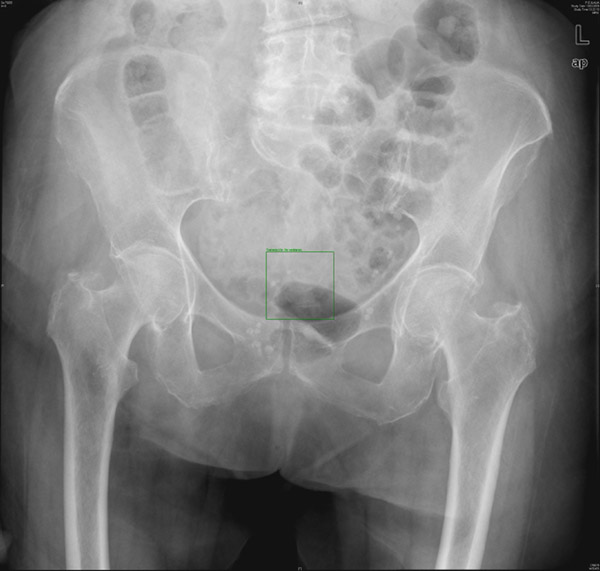

E de Paget